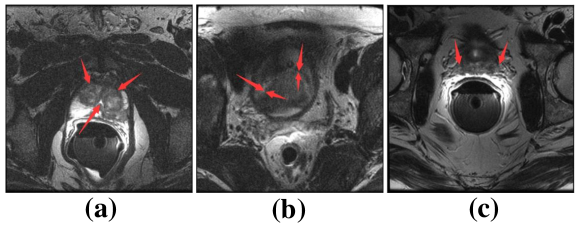

Medical image segmentation is an essential part of medical image analysis. Accurate segmentation of medical image provides very useful information for computer aided diagnosis and treatment of cancers as well as other diseaseszhu2019multi . For instance, segmentation of the liver and tumors plays an important role in hepatocellular carcinoma diagnosis heimann2009comparison . Accurate prostate segmentation is useful for treatment planning and therapeutic procedures for prostate cancerliao2013representation ; zhu2019boundary ; zhu2018exploiting . However, automated medical image segmentation is very challenging for several reasons. Taking prostate segmentation as an example: First, due to many slices only have small part of segmented tissues specifically at the apex and base, which always led to those slices lack of clear boundary and make the automated segmentation fail. Second, imaging artifacts always distribute in the whole image randomly, which negatively influence the process of segmentation. Third, tissues can have a wide variation in size and shape among different slices, which adds to the complexity of segmentation. Fourth, the complex background and fuzzy boundary also make the segmentation process challenging. Furthermore, different from natural images dataset, the size of available medical image dataset is limited. Fig.1 shows examples of prostate MR images. Fig.1(a) shows the phenomenon that imaging artifacts locate in prostate region. Fig.1(b) shows prostate region lacks clear boundary. Fig.1(c) shows the prostate and surrounding tissues have similar intensity distribution. All of above phenomena bring challenges for automated medical image segmentation.

Refer to caption

Figure 1: Challenges in segmenting the prostate from MR images. (a) Noise inside prostate. (b) Weak boundary. (c) Surrounding tissues having similar intensity distribution with prostate.